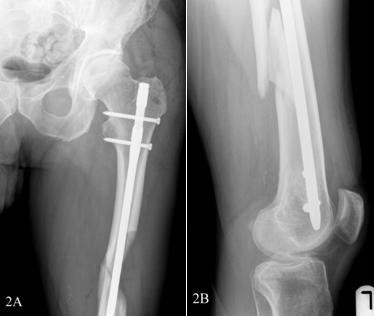

Бедренный интрамедуллярный стержень — это медицинское устройство, предназначенное для стабилизации и ускорения заживления переломов бедренной кости.Он состоит из металлического стержня, который вставляется в полый центр бедренной кости, обеспечивая стабильность и поддержку во время процесса заживления.Гвоздь обычно изготавливается из титана или нержавеющей стали и бывает разных размеров, чтобы соответствовать разным анатомическим особенностям пациента.

После создания точки входа в проксимальном отделе бедренной кости хирург осторожно вводит бедренный интрамедуллярный стержень в костномозговой канал.Для обеспечения точного размещения и выравнивания используется рентгеноскопический контроль.Гвоздь продвигают через кость, выравнивая любые смещенные фрагменты и восстанавливая правильное анатомическое выравнивание.

После того, как гвоздь будет правильно расположен, вставляются стопорные винты, чтобы зафиксировать гвоздь в кости.Эти винты обеспечивают дополнительную стабильность и предотвращают ротационные или осевые движения фрагментов перелома.Количество и расположение винтов зависят от характера перелома и предпочтений хирурга.